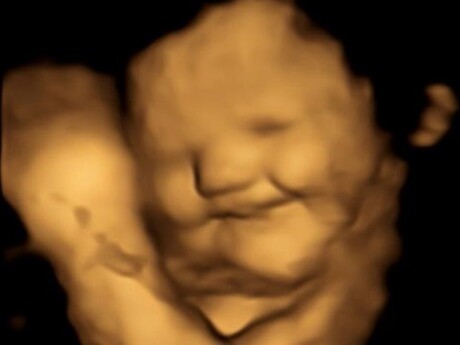

Babies observed reacting to taste and smell in the womb

Humans experience flavour through a combination of taste and smell; in foetuses, it is thought that this might happen through inhaling and swallowing the amniotic fluid in the womb. Now, scientists claim to have recorded the first direct evidence that foetuses react differently to various smells and tastes by observing their facial expressions.

Researchers from Durham University’s Fetal and Neonatal Research Lab took 4D ultrasound scans of 100 pregnant women to see how their unborn babies responded after being exposed to flavours consumed by their mothers. The research team, which also included scientists from Aston University and the French National Centre for Scientific Research (CNRS) at the University of Burgundy, scanned the mothers at both 32 and 36 weeks of pregnancy to see how the foetuses reacted to either carrot or kale flavours.

Facial reactions seen in both flavour groups, compared with foetuses in a control group who were not exposed to either flavour, showed that exposure to just a small amount of carrot or kale flavour was enough to stimulate a reaction. Foetuses exposed to carrot showed more ‘laughter-face’ responses, while those exposed to kale showed more ‘cry-face’ responses. The results were published in the journal Psychological Science.